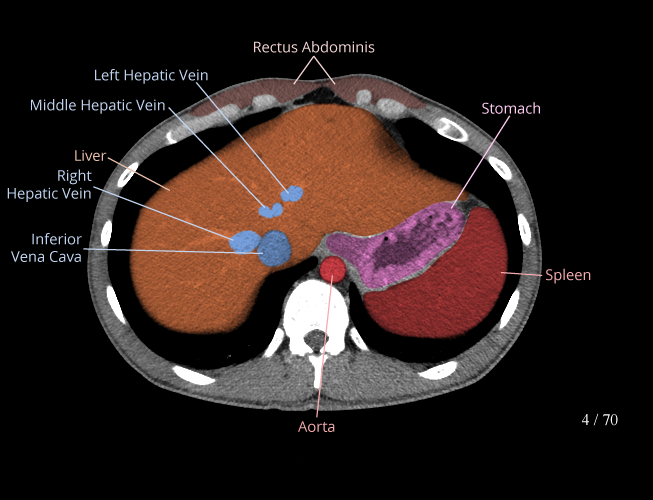

Body

Covers abdominal CT anatomy.